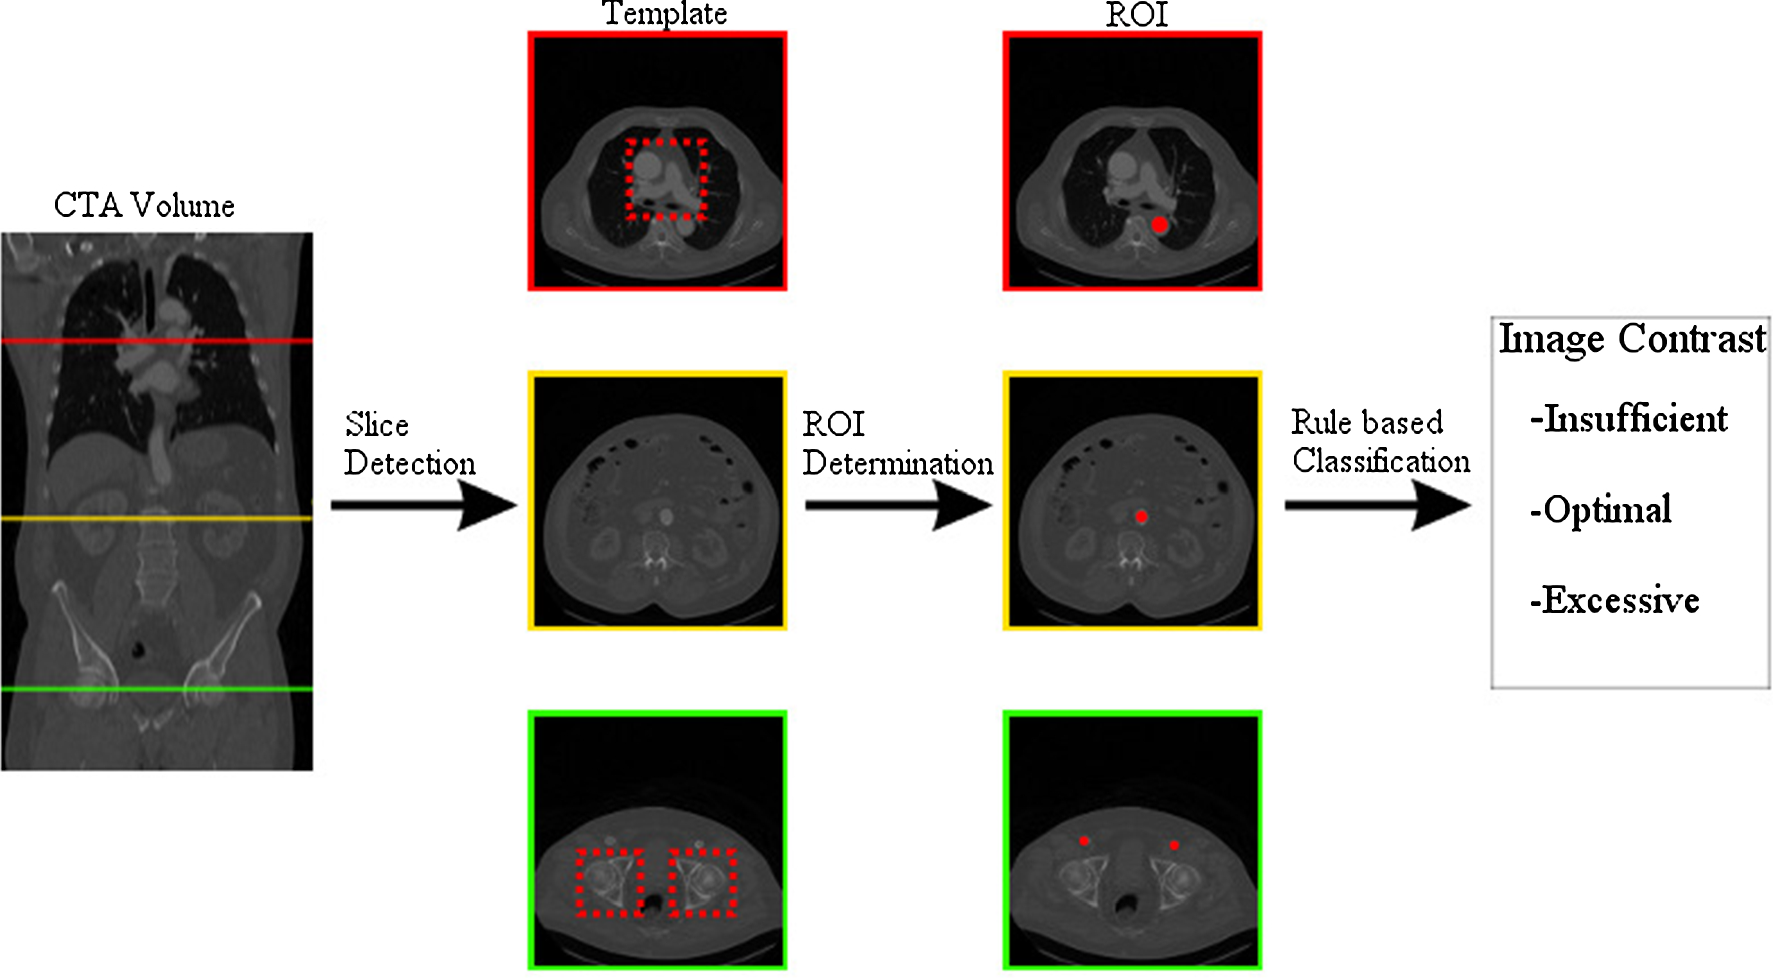

Fig. 1

This graphic gives an overview of the three major components of the automatic image contrast measurement process

To circumvent the time-consuming task of assessing the image contrast by experts we propose a method for an automatic image quality measurement of aortic CTA volumes. The assessment is implemented as a rule-based classification based directly on the HU values of 2D ROIs distributed over the CTA volume. Our approach consists of three consecutive components as shown in Fig. 1. The first step is to detect the slices suitable for the ROIs. We applied a template matching as this method is a staple in medical image processing and showed success in various use cases [5, 7]. Following this is the automatic ROI determination. The ROIs are positioned in the aorta and the arteria femoralis communis, respectively, and are determined by combining the circle Hough transform [3] and the vessel filter [6] for smaller structures. Taking the mean HU of each ROI a rule-based approach was applied. The rules were defined by radiological experts to assign the data set to one of the following three classes: insufficient image contrast, optimal image contrast or excessive image contrast.